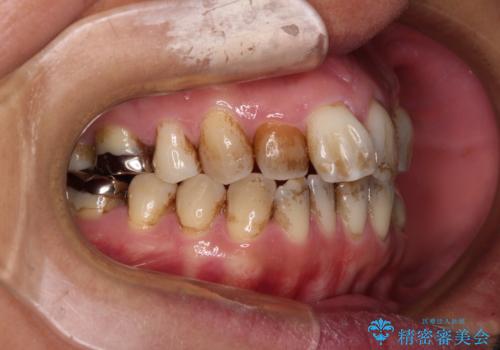

前歯の後戻り インビザラインでの再矯正治療

- かつて抜歯矯正を行ったものの、後戻りをしてしまったとのことで来院された患者様です。

上顎前歯が前突し、隣の歯が裏側に移動してきている状態でした。

舌のトレーニングをしっかりと行ってくださり、10ヶ月で希望通りの歯列となりました。

日頃から飲まれる飲み物の影響で着色しやすいため、来院の度に着色除去のクリーニングも行っていました。